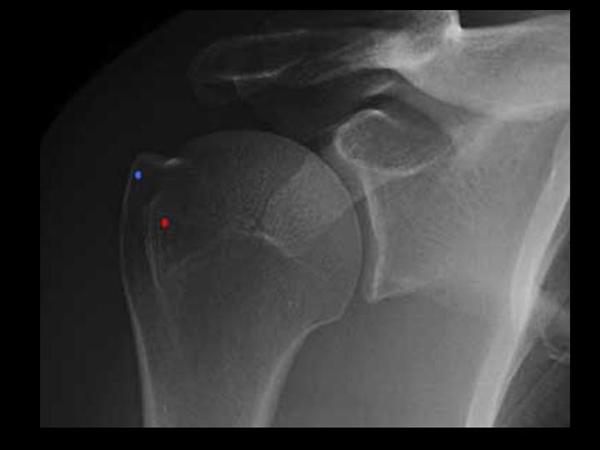

1. shoulder AP

glenohumeral joint space, DJD

Hill Sachs 를 확인하기 위해 ER/IR 해볼 수 있습니다..